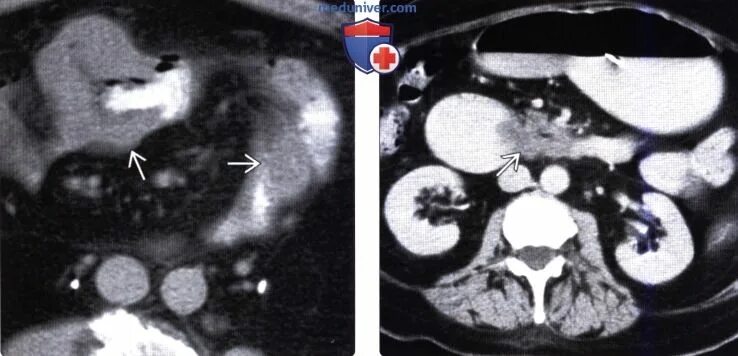

Метастазы при лимфоме